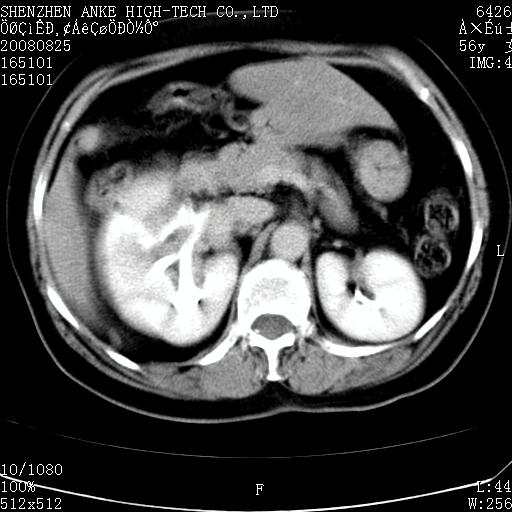

患者,女性,56岁,腰痛3年,查:右腹部约8x10cm肿块,固定,无压痛;8月23日在外院做了平扫,发现右肾巨大肿块(外院具体诊断不祥);今天在我院做了静脉肾盂造影,示:右肾明显增大,分泌功能明显减弱。

1)考虑右肾癌并右肾静脉瘤栓形成。2)脂肪肝。